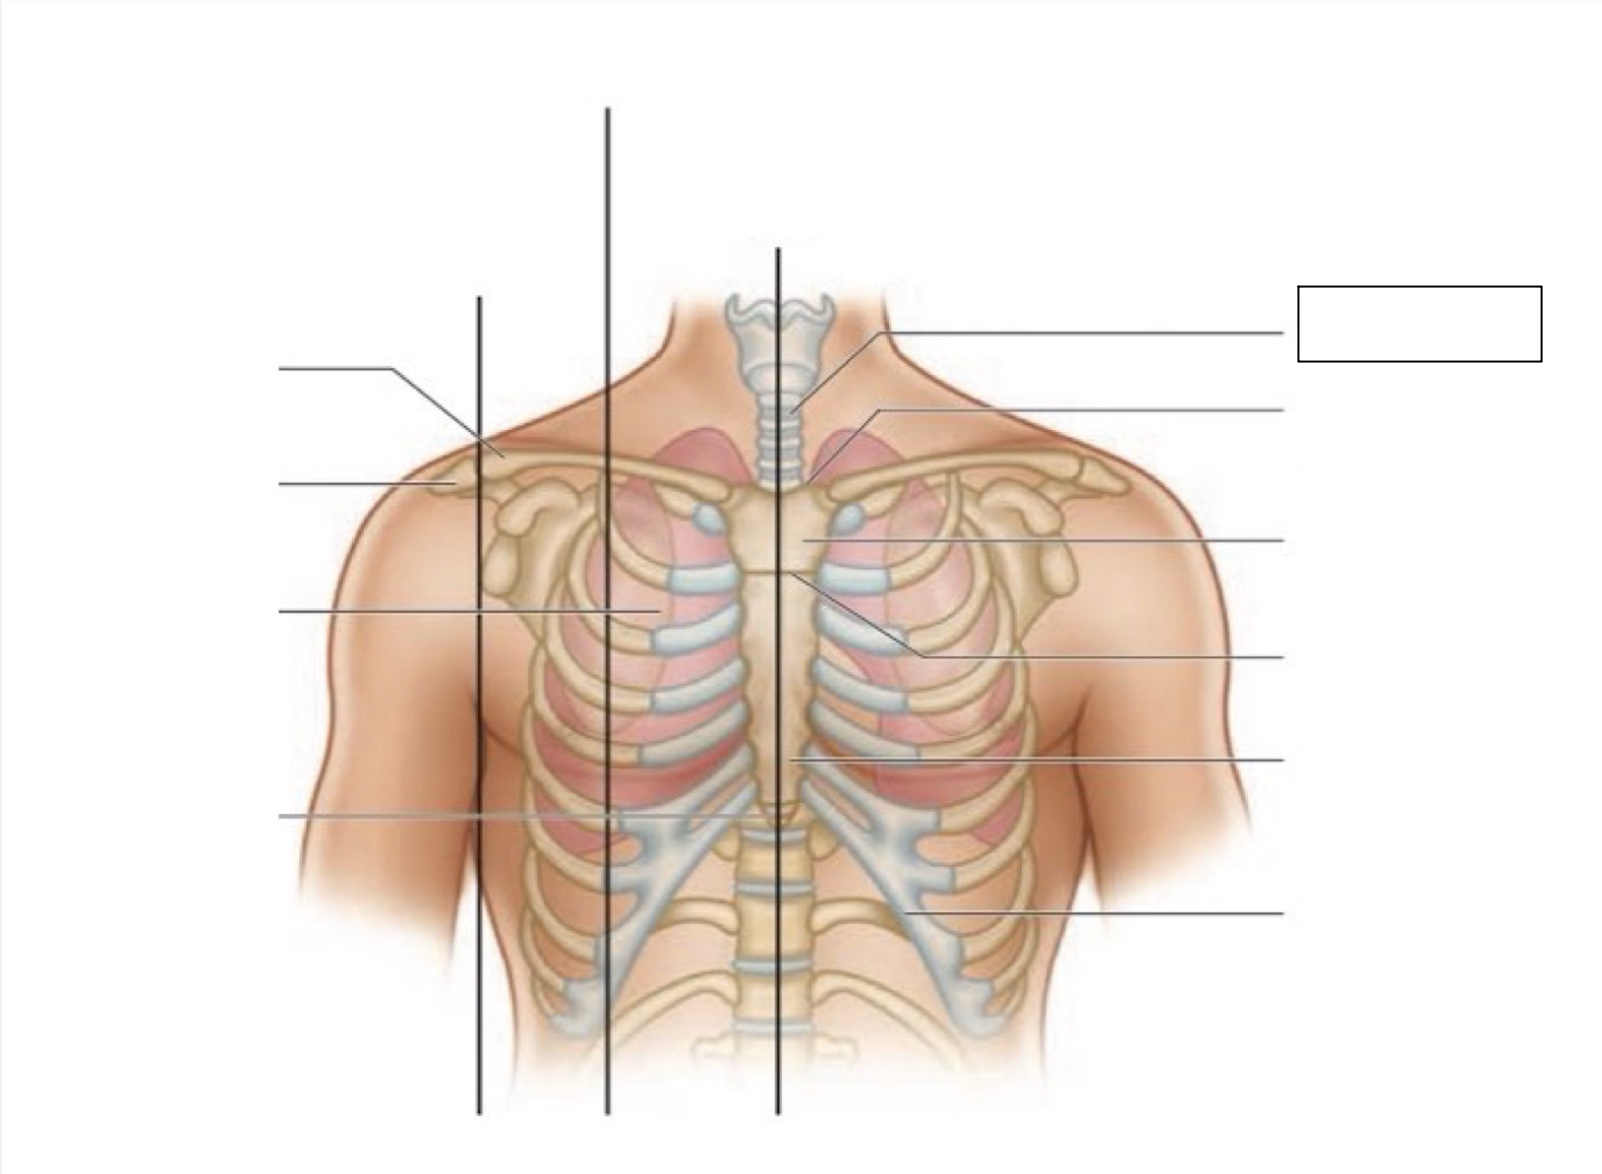

midsternal line

trachea

suprasternal notch

manubrium

angle of Louis

sternum

costal margin

xiphoid process

intercostal space

acromion

clavicle

anterior axillary line

midclavicular line

inferior angle of scapula

scapula

midscapular line

midspinal line

spinous process